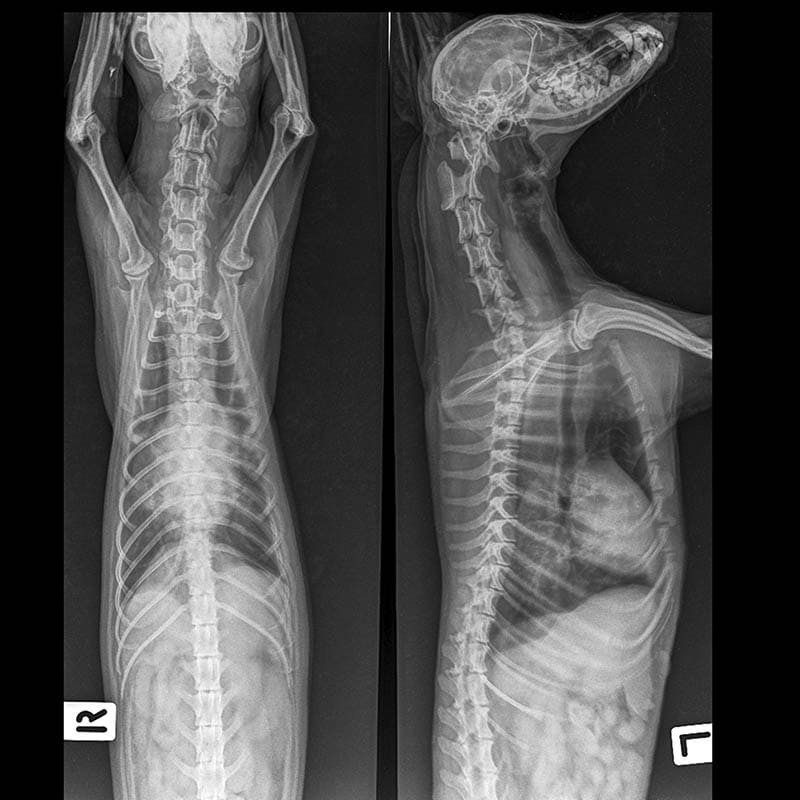

Learn more »Unusual or labored breathing is a major cause for concern among dog parents. In normal conditions, your dog should subtly move their chest when breathing, with minimal movement of their abdomen. If your dog moves their abdomen when breathing, it is because they are making an extra effort to breathe air in or out. A dog’s stomach is located within the abdomen, sometimes mistakenly referred to as breathing from the stomach, while it’s actually the abdomen. If your dog’s chest and abdomen are moving when they breathe, accompanied by other signs like flared nostrils, nasal discharge, extended neck, blue gums, elbows sticking out, coughing, noisy breathing or heavy panting, and shallow breathing, they may be suffering from dyspnea – having difficulty breathing.

Dyspnea occurs when a dog is having to work harder than usual to breathe, resulting in labored or shallow breathing. If your dog is displaying signs of dyspnea, this is an emergency situation and they need to be seen by a vet immediately.